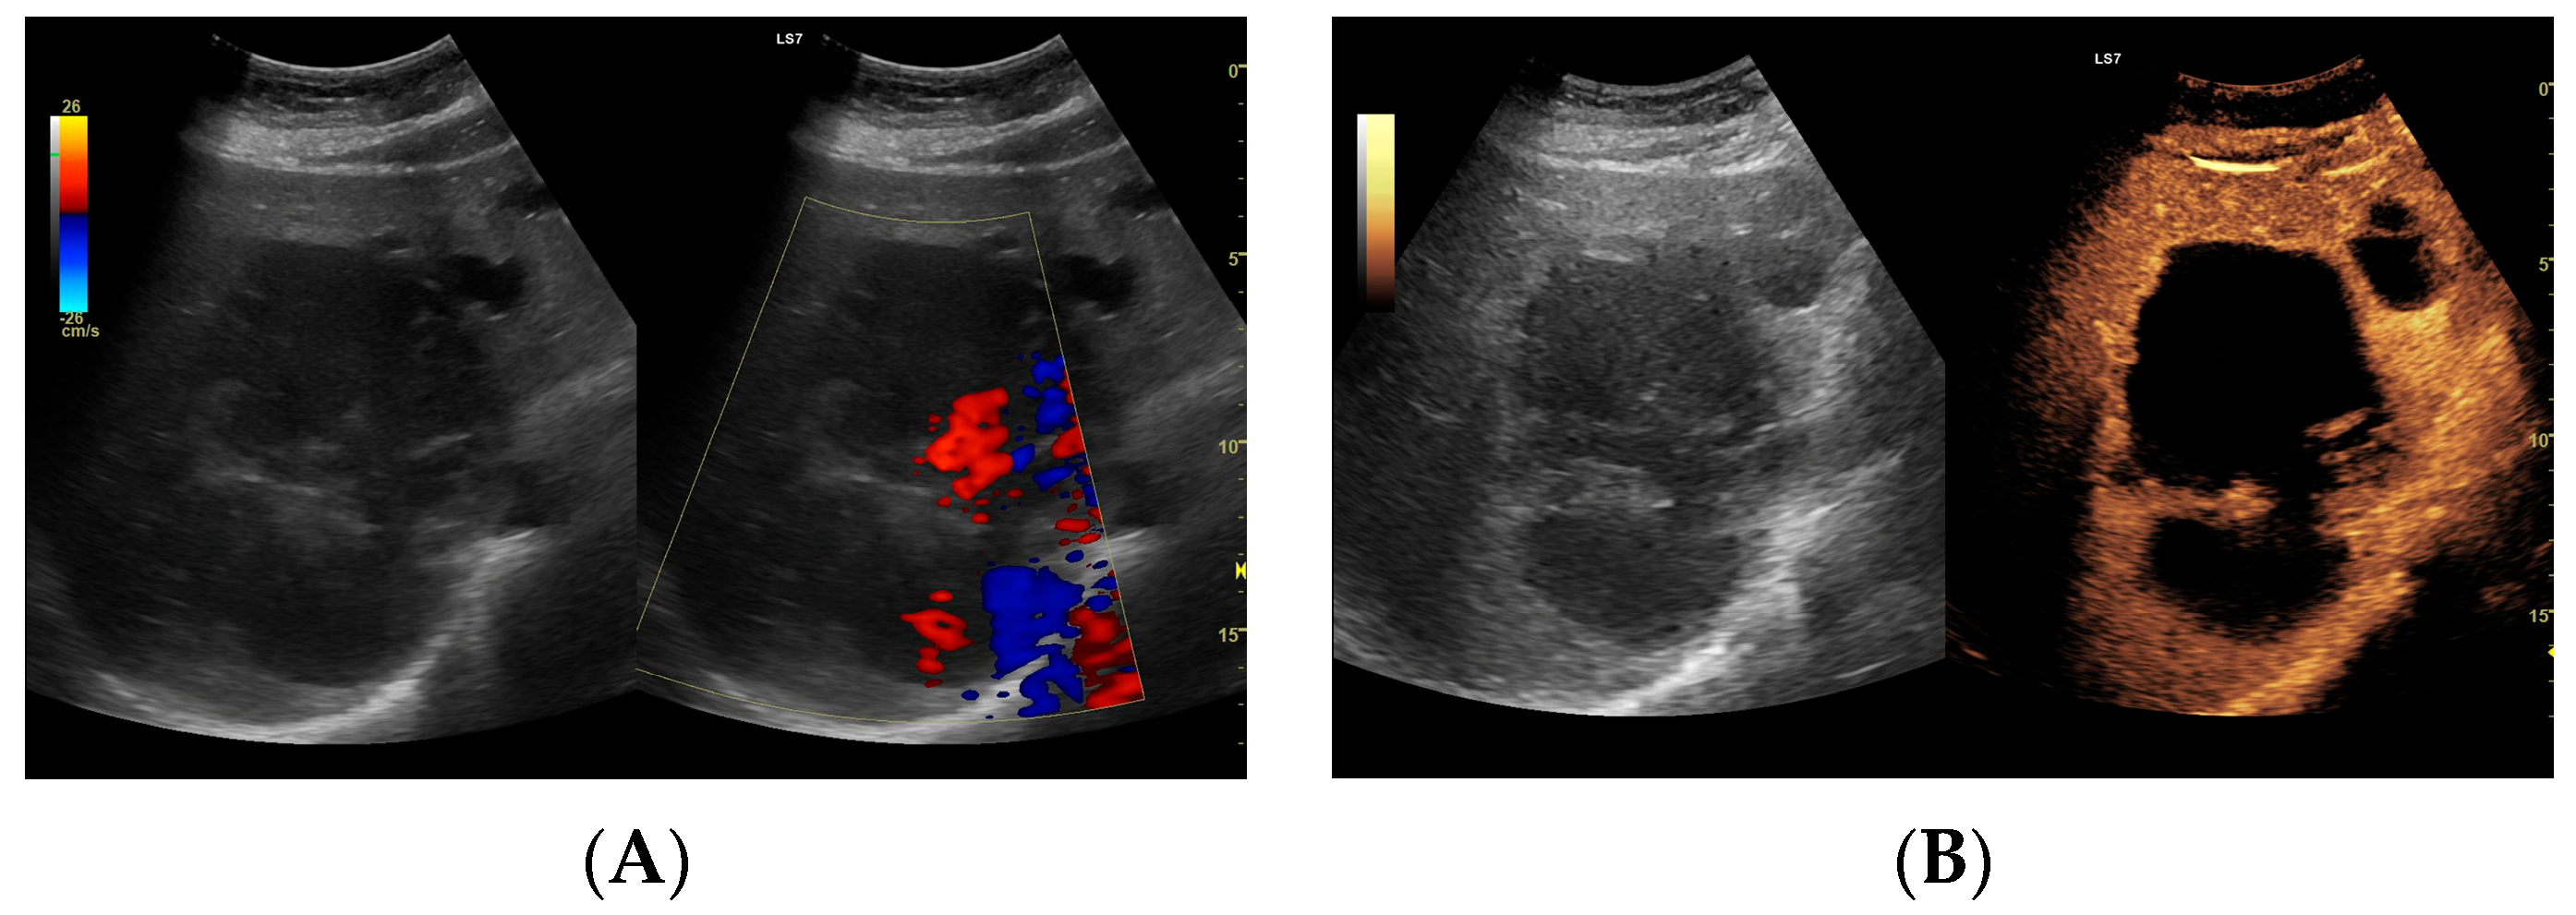

Figure 8.

Focal liver lesion diagnosed as a type III abscess. (A) Post-contrast image on CT. (B) B-mode ultrasound: the fluid component of the lesion is difficult to define. (C) CEUS: the fluid component of the lesion is visible, and the patient is qualified for percutaneous drainage. (D) Post-contrast image on CT: Follow-up examination one week after placement of drains shows a visible reduction in the fluid component. The lesion is transitioning from type III to type II, with a visible “honeycomb” sign. (E) B-mode ultrasound: the fluid component of the lesion remains challenging to define. (F) CEUS: the fluid component of the lesion is visible, indicating regression from stage III to II. (G) Post-contrast image on CT: follow-up examination performed 1.5 months after placement of percutaneous drainage reveals a visible residual lesion. (H) B-mode ultrasound: a residual lesion is visible. (I) CEUS: the residual lesion shows the fluid component to be completely invisible, with a connective tissue scar present.